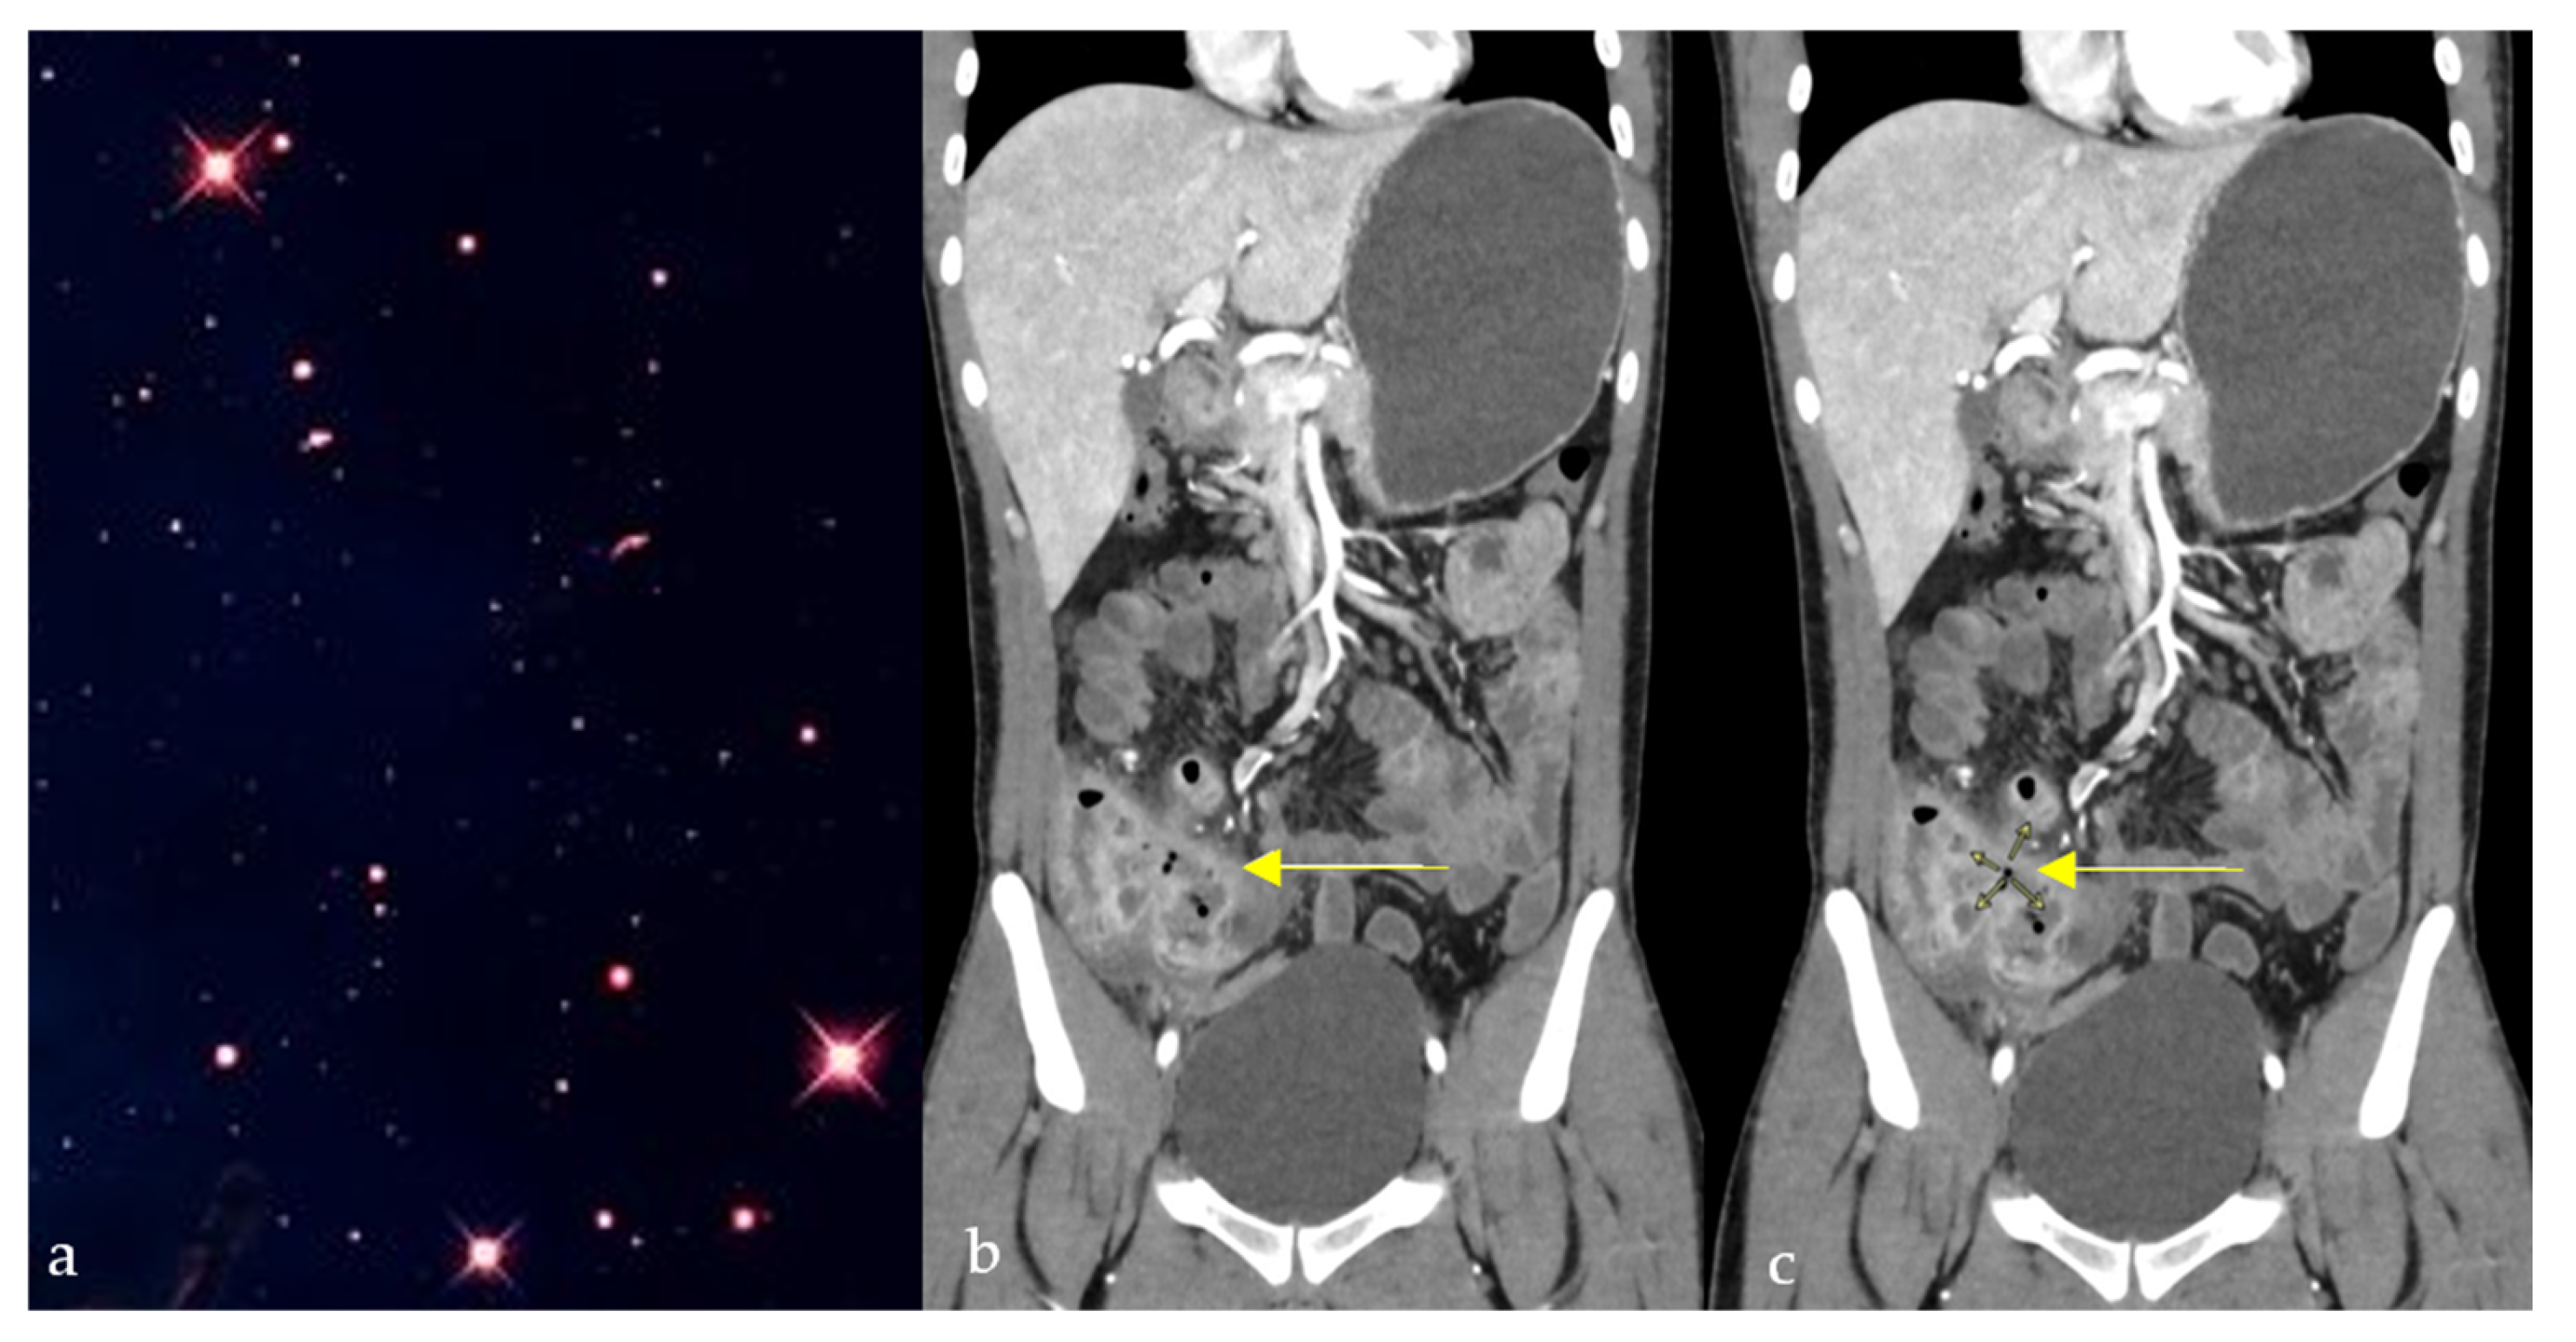

2.7. Star Sign